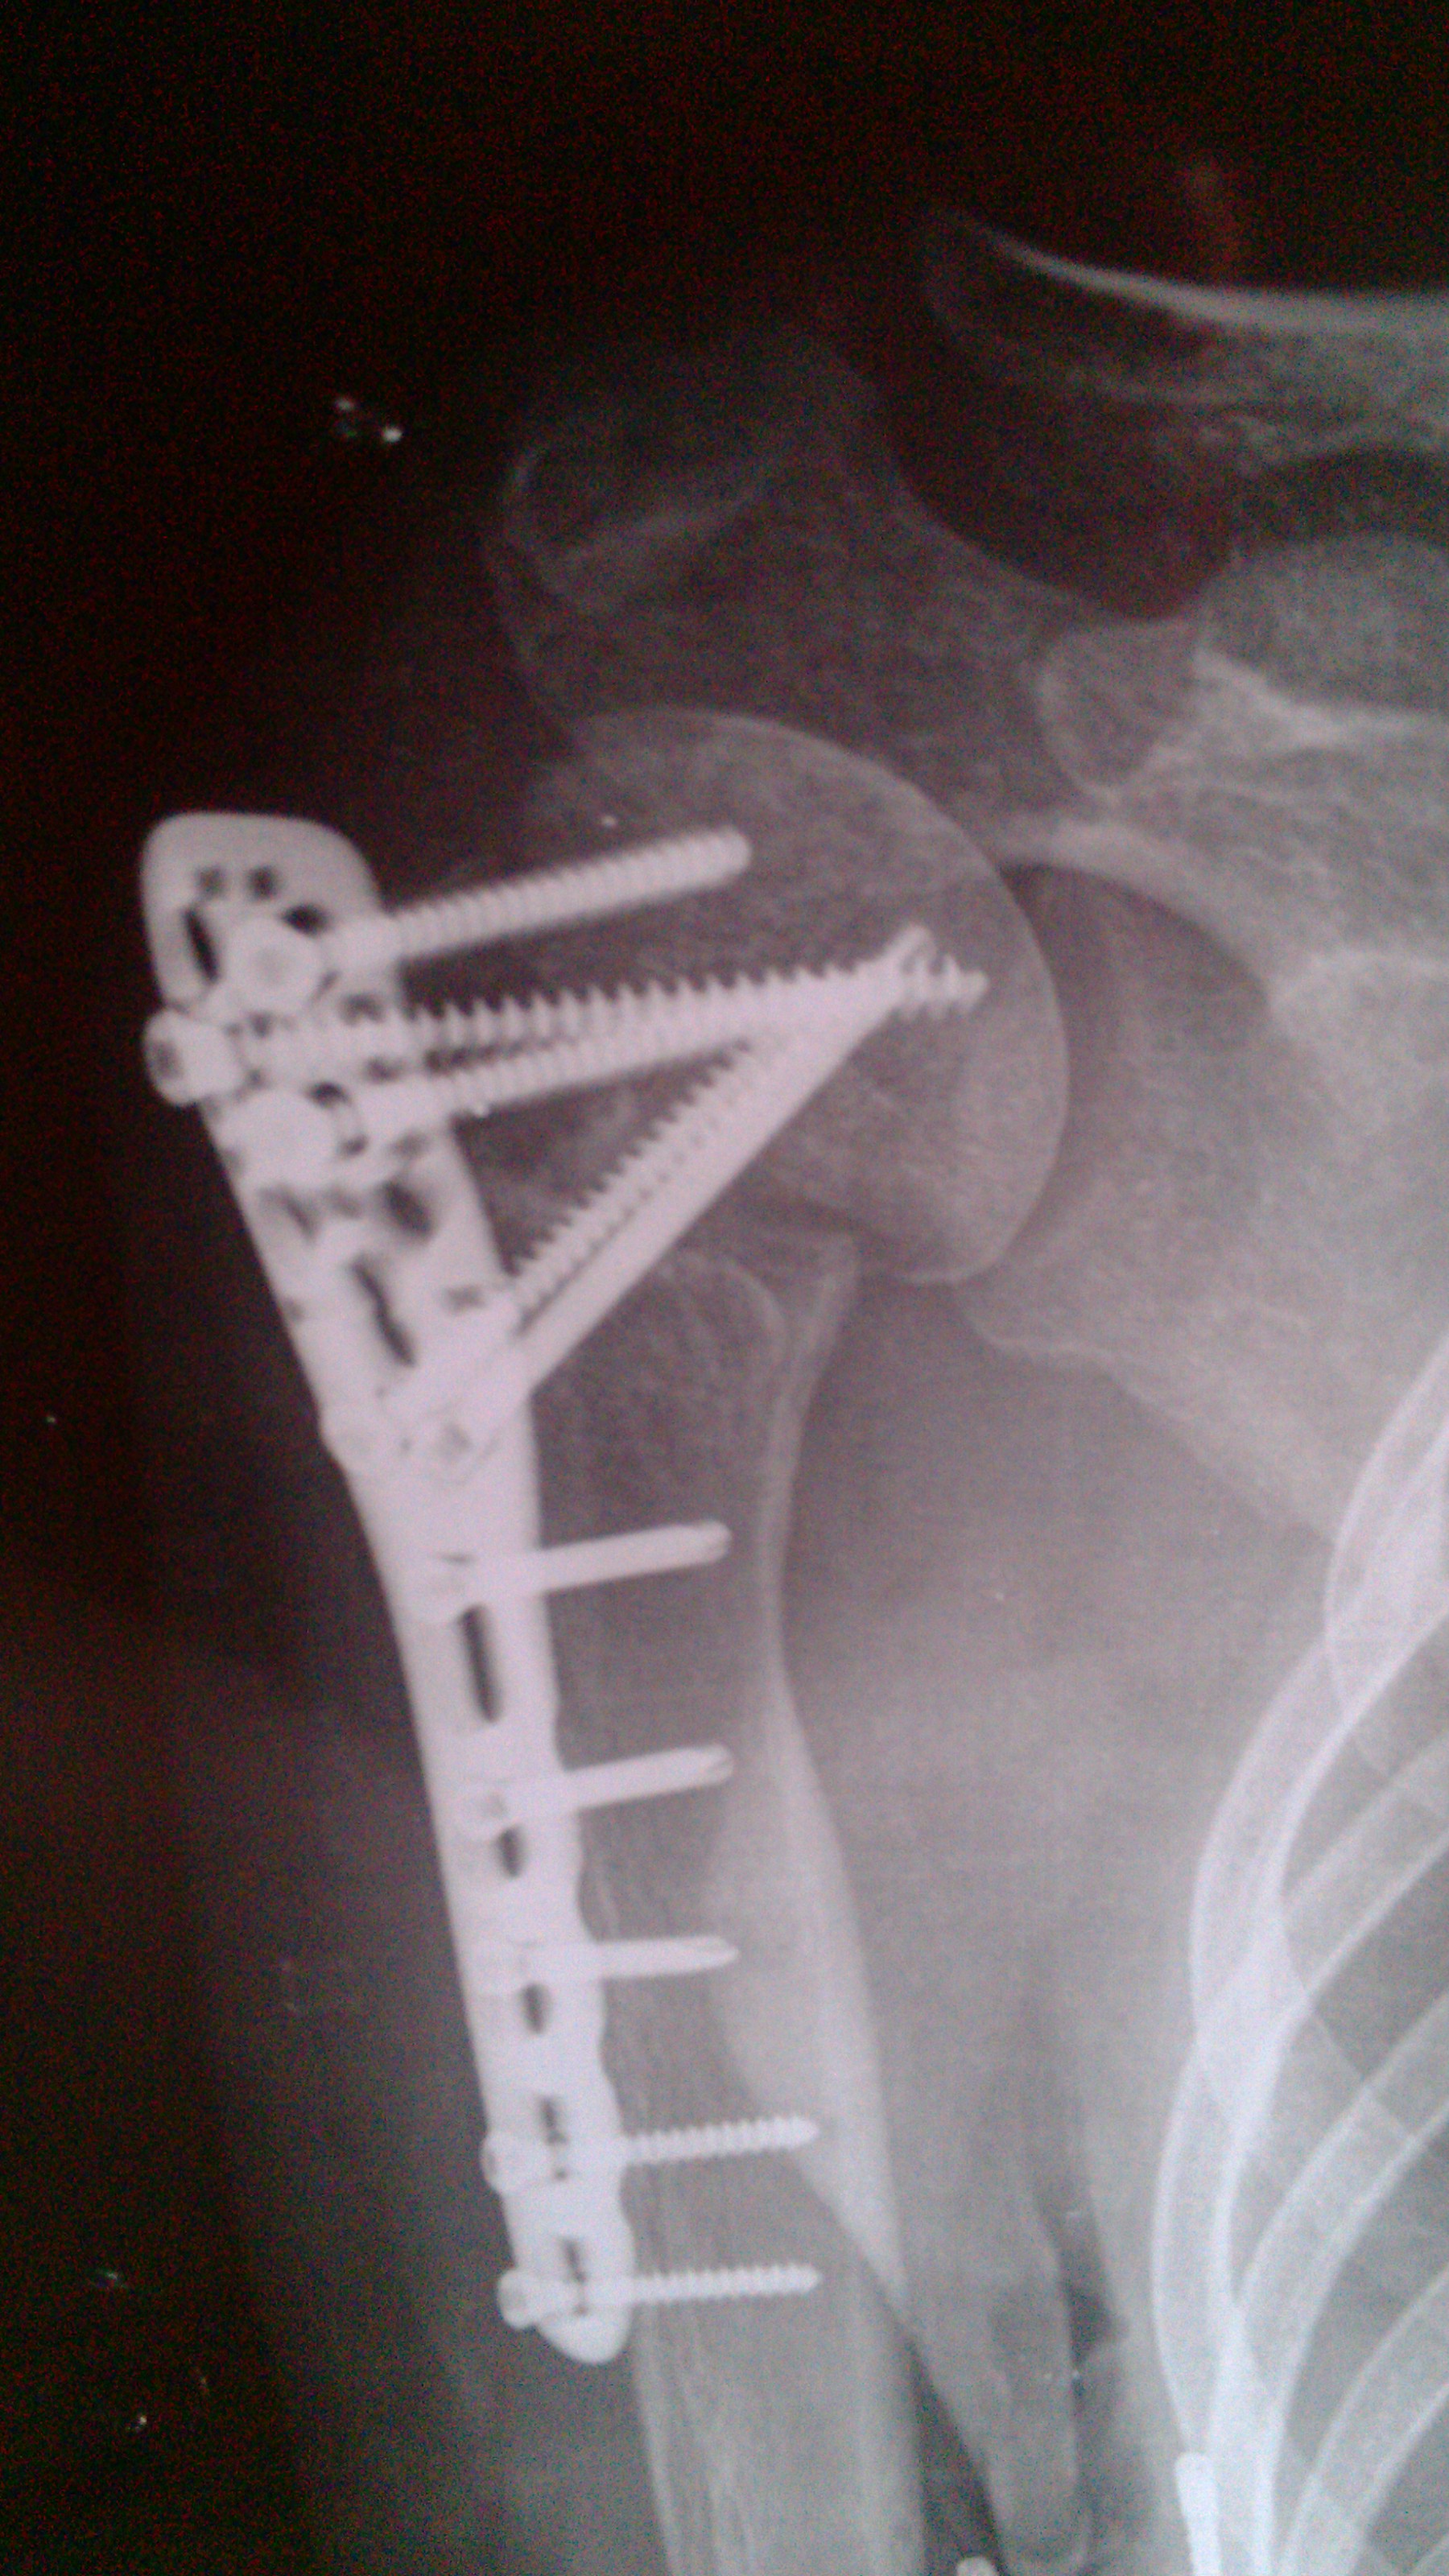

奥 奥德赛 声名鹊起 正式会员 注册 2012/11/14 帖子 197 获得点赞 1 声望 0 年龄 57 2013/07/23 #37 王家祥 说: 骨痂较上月好,可以配合内服补中益气汤! 点击展开... 王老师,你好! 自上次向你咨询后至今已快两个月了,这两个月都一直在内服汤药配合丸药,并配合艾灸,今天又去重庆骨科医院摄了片,接诊医生叫继续服药。现在我将这次摄的片发上来,请老师帮忙诊断一下,下一步该如何进行?因为本病人骨折至今已近一年了,今后究竟该如何治疗,还望老师多多指教,在下替病人向王老师致谢谢了! 附件 IMG_20130723_184244.jpg 1.3 MB 查看: 28 IMG_20130723_183945.jpg 1.1 MB 查看: 27

王家祥 说: 骨痂较上月好,可以配合内服补中益气汤! 点击展开... 王老师,你好! 自上次向你咨询后至今已快两个月了,这两个月都一直在内服汤药配合丸药,并配合艾灸,今天又去重庆骨科医院摄了片,接诊医生叫继续服药。现在我将这次摄的片发上来,请老师帮忙诊断一下,下一步该如何进行?因为本病人骨折至今已近一年了,今后究竟该如何治疗,还望老师多多指教,在下替病人向王老师致谢谢了!

王家祥 闻名全坛 正式会员 注册 2010/07/07 帖子 18223 获得点赞 403 声望 113 年龄 48 2013/07/24 #38 奥德赛 说: 王老师,你好! 自上次向你咨询后至今已快两个月了,这两个月都一直在内服汤药配合丸药,并配合艾灸 点击展开... 片子不是很清晰,但可以看得出骨痂较前好。建议配合外敷药。可以用我的那个陈伤的药方。目的是温通局部。

奥德赛 说: 王老师,你好! 自上次向你咨询后至今已快两个月了,这两个月都一直在内服汤药配合丸药,并配合艾灸 点击展开... 片子不是很清晰,但可以看得出骨痂较前好。建议配合外敷药。可以用我的那个陈伤的药方。目的是温通局部。